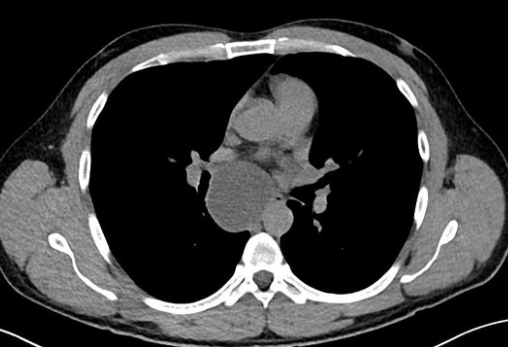

Ground glass opacification

A

1. Pulmonary oedema

2. Pulmonary haemorrhage

3. Atypical infection (PCP, CMV)

4. ARDS

ARDs vs pulmonary oedema: normal size heart and no pleural effusion in ARDS